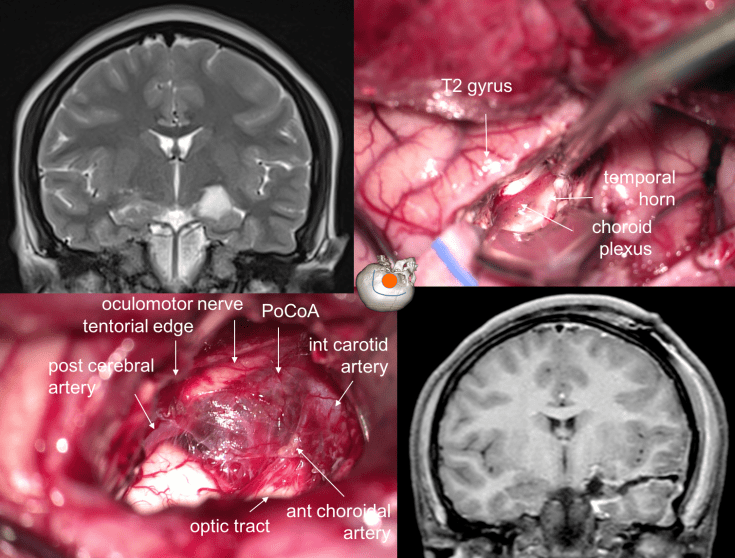

les tumeurs temporales

lorsqu’elles sont situées à la face interne, elle adhérent volontiers au plan vasculo-nerveux interne, englobant parfois le nerf oculo-moteur et pouvant adhérer intimement à la carotide, l’artère communiante postérieure, l’artère cérébrale postérieure. l’imagerie pré-opératoire permet difficilement de prévoir cette difficulté, qui peut interdire une exérèse complète.

la résection anatomique temporo-pôlaire peut être le premier temps d’une résection temporale interne (hippocampectomie) dont l’étendue est dictée par l’extension tumorale, et peut être aidée par l’IRM per-opératoire

les tumeurs localisées à la face interne du lobe temporal plus haut situées, au contact de la bandelette optique, peuvent être abordées en conservant le pôle temporal par un abord trans-ventriculaire trans-T2 (ci-dessous)